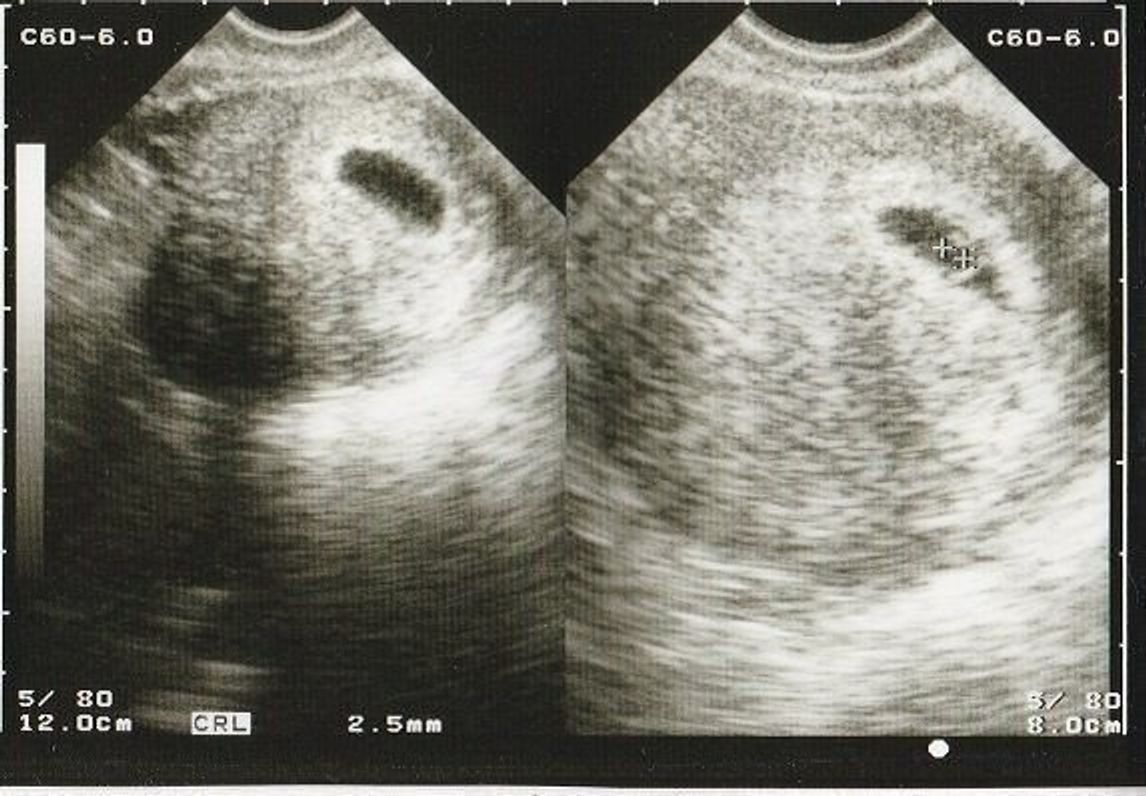

7週目、体外受精で始めての妊娠です! 6週5日目が 卵黄囊確認ですが胎嚢が105mm (エコー左上) 7週1日目でセカンドオピニオンして、 中身は空っぽで、胎嚢は132mm (エコー右上) 本日いつも行っている所で再検査した.